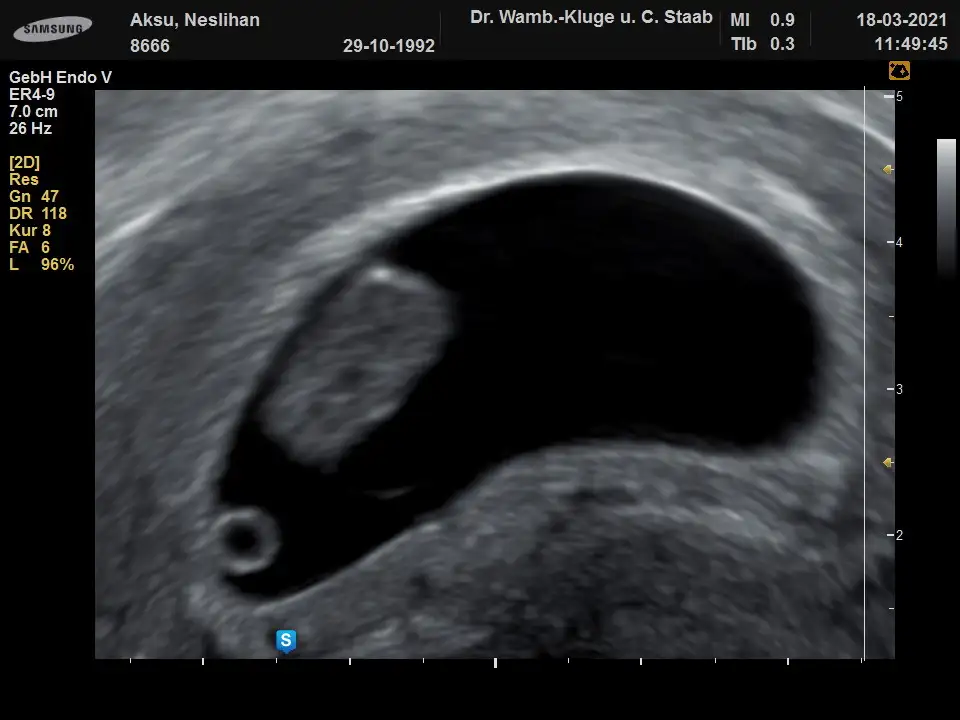

Banada bakabilirmisin lutfen vajinal ult. 9hafta

• 8666_20210318-115037_7.webp

• 8666_20210318-114945_5.webp